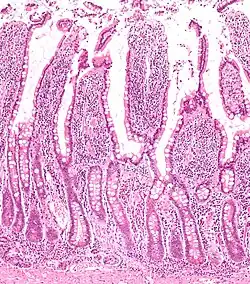

Micrograph of the small intestine mucosa showing the intestinal villi and crypts of Lieberkühn.

The three sections of the small intestine look similar to each other at a microscopic level, but there are some important differences. The parts of the intestine are as follows: